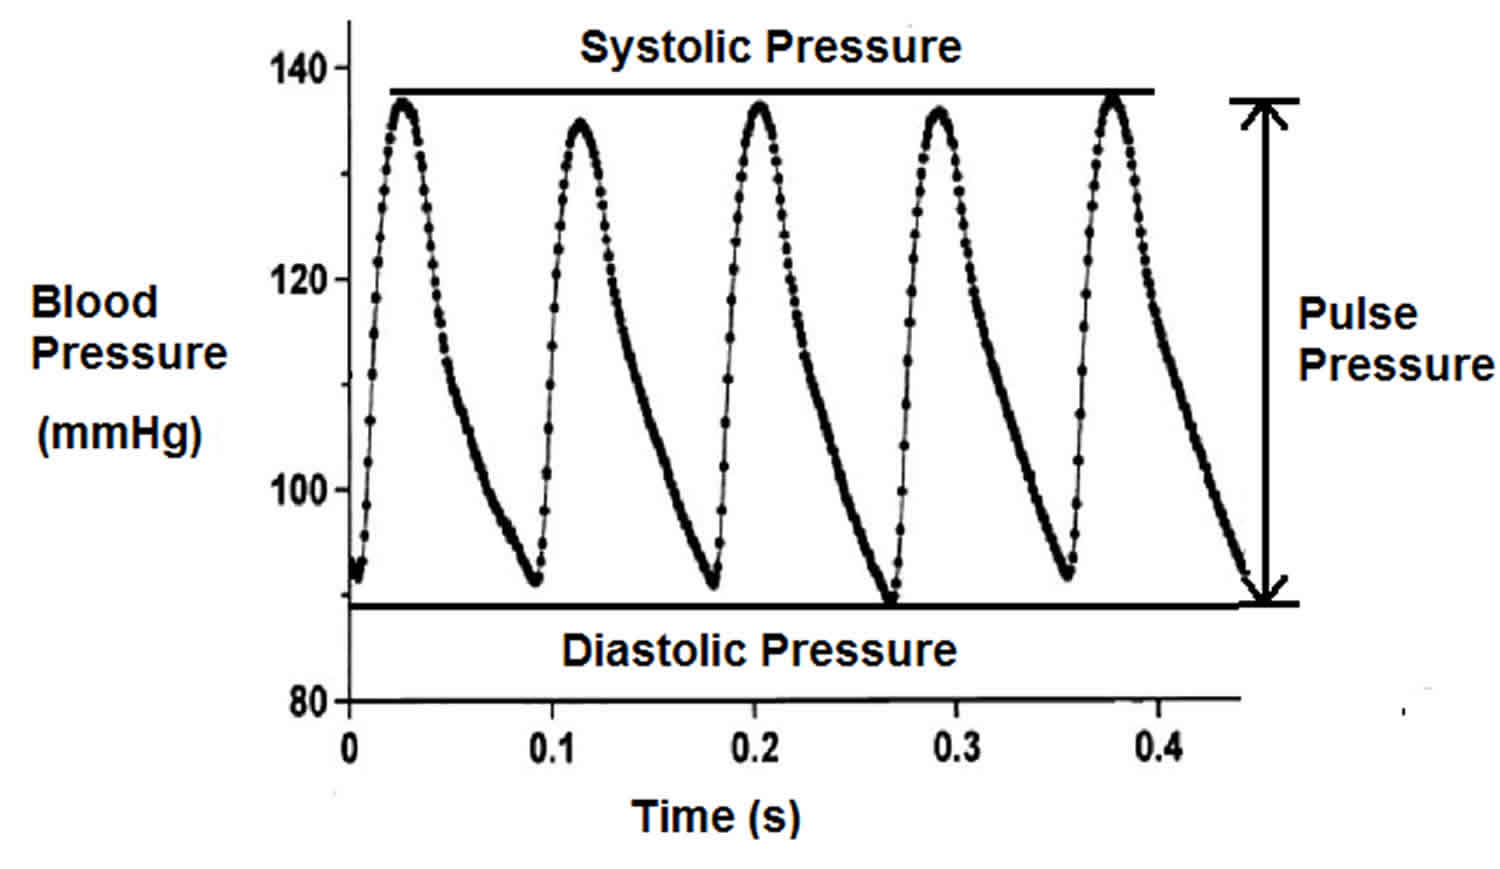

Pulse Pressure Virtgz

https://healthjade.net/wp-content/uploads/2020/01/pulse-pressure.jpg